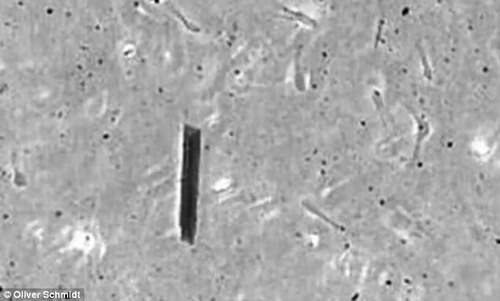

Vi vật thể này là một ống nano kim loại (màu xám đen) bên trong có chứa tinh trùng của bò. Trong tương lai, nó có thể phục vụ cho mục đích thụ thai hoặc vận chuyển thuốc tới bất kỳ nơi nào trong cơ thể.

| Robot chứa tinh trùng . |

Oliver Schmidt - nhà khoa học tại Viện nghiên cứu Integrative Nanosciences ở Dresden (Đức), cho biết để tạo ra tinh trùng robot này, các nhà khoa học đã dùng một vi ống có đường kính khoảng 0,005-0,008 mm và chiều dài 0,05 mm làm từ sắt và nano titan. Tinh trùng thật sẽ được chứa ở bên trong. Sau đó, các nhà khoa học dùng từ trường đễ điều khiển hướng của ống kim loại, dẫn robot này đi theo hướng mà họ muốn.